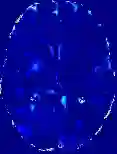

Accurate infarct segmentation in non-contrast CT (NCCT) images is a crucial step toward computer-aided acute ischemic stroke (AIS) assessment. In clinical practice, bilateral symmetric comparison of brain hemispheres is usually used to locate pathological abnormalities. Recent research has explored asymmetries to assist with AIS segmentation. However, most previous symmetry-based work mixed different types of asymmetries when evaluating their contribution to AIS. In this paper, we propose a novel Asymmetry Disentanglement Network (ADN) to automatically separate pathological asymmetries and intrinsic anatomical asymmetries in NCCTs for more effective and interpretable AIS segmentation. ADN first performs asymmetry disentanglement based on input NCCTs, which produces different types of 3D asymmetry maps. Then a synthetic, intrinsic-asymmetry-compensated and pathology-asymmetry-salient NCCT volume is generated and later used as input to a segmentation network. The training of ADN incorporates domain knowledge and adopts a tissue-type aware regularization loss function to encourage clinically-meaningful pathological asymmetry extraction. Coupled with an unsupervised 3D transformation network, ADN achieves state-of-the-art AIS segmentation performance on a public NCCT dataset. In addition to the superior performance, we believe the learned clinically-interpretable asymmetry maps can also provide insights towards a better understanding of AIS assessment. Our code is available at https://github.com/nihaomiao/MICCAI22_ADN.